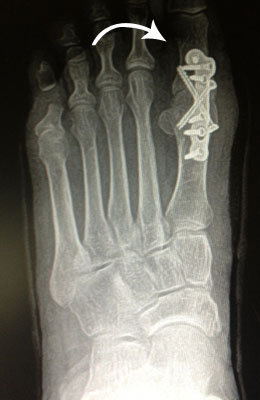

Bunion with Hammertoe Surgery

Before and after of a bunion with hammertoe deformity correction, with drifting of the 1st and 2nd toes towards each other. Both toes are now realigned behind their respective joints, with removal of the prominence at the great toe joint. See more bunion before and after pictures.